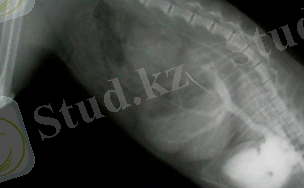

1-сурет. Мысықтың аортасында қан ұйығы көрсетілген.

Сонымен қатар, тромб артқы аяқтардың толық параличінде көрінуі мүмкін, бұлшықеттер қатай бастайды, жанасу ауырсынуды тудырады.

Бұл суретте мысықтың қан ұюы (сол жақ қарыншада) .